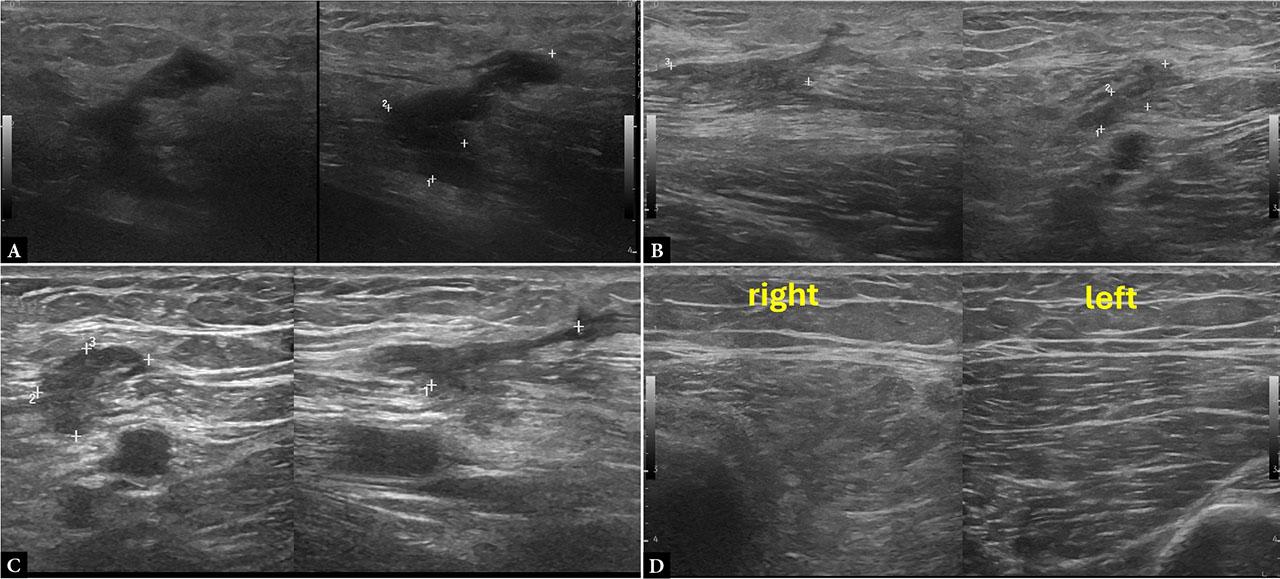

Given the mechanism of injury and clinical findings, a US examination was performed, revealing an intramuscular hematoma within the right rectus femoris muscle. Serial US evaluations were performed within a month of each other to monitor the evolution of the post-traumatic hematoma. Over time, progressive reduction in size was observed, along with changes in echotexture consistent with hematoma resorption. No significant vascular signal was detected on CD examination. However, the patient reported a difference in muscle strength in the right leg. Comparative imaging revealed hypotrophy and increased echotextural inhomogeneity of the right rectus femoris compared with the contralateral side, consistent with evolving post-traumatic muscle remodeling and potential disuse atrophy (Fig. 3).

Ultrasound of the right rectus femoris muscle showing a heterogeneous hypoechoic lesion (1.2 × 1.6 × 2.7 cm) without internal flow on CD (A). Follow-up examinations at one (B) and four weeks (C) demonstrate progressive reduction in size (from 1.2 × 1.3 × 1 cm to 1.3 × 0.5 cm) and increasing echogenicity, consistent with resorptive hematoma evolution. Mild subcutaneous tissue edema persisted throughout the follow-up period. Comparative imaging (D) highlights muscle asymmetry and echotextural inhomogeneity, suggestive of evolving structural remodeling

Educational tip: When assessing muscle trauma, always scan from origin to insertion in both longitudinal and transverse planes. Monitor the echogenic evolution of hematomas over time, typically progressing from hypoechoic (acute phase) to echogenic (chronic/ resorptive phase). Pay close attention to secondary signs such as muscle hypotrophy or asymmetry, especially during later follow-ups, as these may reflect disuse or incomplete functional recovery.

Clinical correlation: Post-traumatic hematomas follow a predictable course unless complicated. Progressive healing (size reduction, increasing echogenicity) supports a conservative approach. However, persistent asymmetry, altered echotexture, or strength deficits may indicate delayed functional recovery or evolving fibrosis. Such findings justify a personalized rehabilitation strategy and continued imaging surveillance in selected cases.